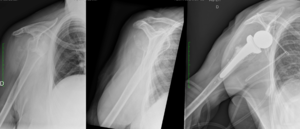

Reverse shoulder arthroplasty is a more reliable treatment than hemiarthroplasty for complex proximal humerus fractures at least in elderly patients because its functional outcomes appear to depend less on tuberosity healing and rotator cuff integrity (Figure).[90]

Reverse shoulder athroplasty for fracture. Frontal, axial and lateral Lamy radiographs after a reverse total shoulder implant. Note the lower positioning of the glenoid baseplate, the satisfactory reconstruction of the tuberosities, and the absence of cement at the autograft level.

Reverse shoulder arthroplasty for malunion of proximal humeral fracture. A) Anteroposterior radiograph of a malunited proximal humerus fracture; B) post-operative radiograph of the fracture sequelae treated with reverse shoulder arthroplasty.